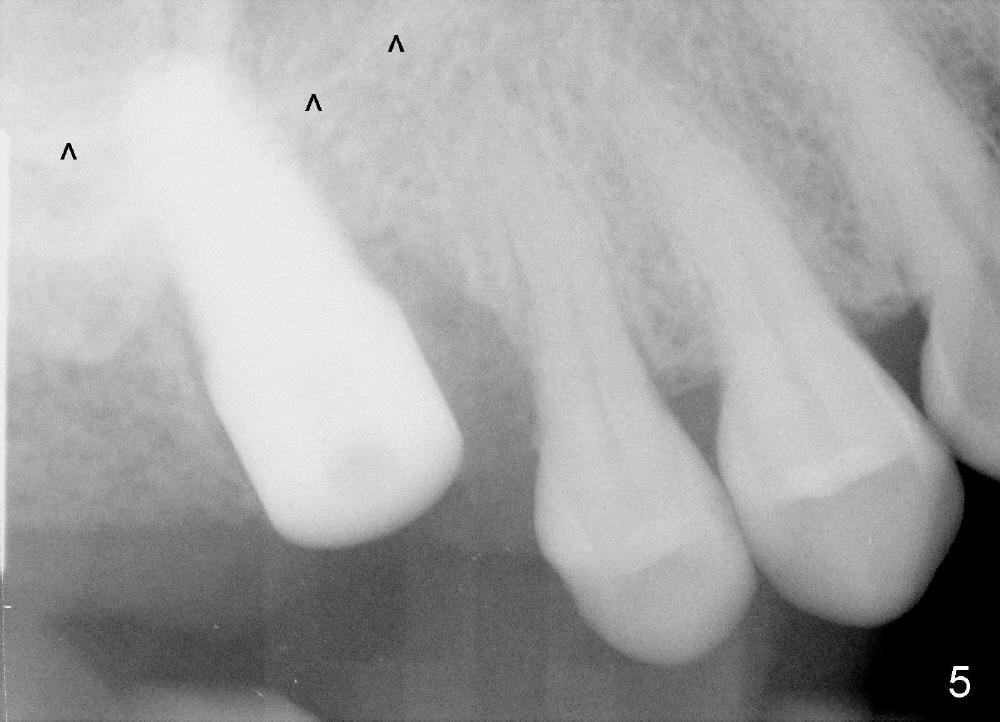

The upper right 1st molar fractures, the lingual portion mobile (Fig.1). There are deep pockets mesiolingually and distolingually. Fig.2 is preop PA, showing mesial bone resorption (*). The 84-year-old lady agrees extraction and immediate implant. Extraction is difficult due to not only root fracture but also hemorrhage. Following debridement of granulation tissue, the 3 sockets are packed with gauze for hemostasis. Even so, there is oozing from the bone. The septum can not be seen clearly. Its position is determined by an explorer. Osteotomes have to be used for osteotomy in the septum, followed by taps. The first intraop PA shows that 5x20 mm tap penetrates the sinus floor (Fig.3 ^). The osteotomy is further enlarged until 7x17 mm tap with stability (Fig.4). So far there has been no sign of sinus membrane perforation. Mixture of freeze dry mineralized bone and Osteogen is placed in the socket and pushed to the buccal and lingual walls as well as into sinus using a 4 mm flat end osteotome. A 7x17 mm implant is initially difficult to be inserted possibly due to blockage by bone graft. The osteotomy have to be recreated by a series of osteotomes and taps before placement of the 7x17 mm implant. It appears that the apical threads have been engaged into the sinus floor for primary stability (Fig.5). The insertion torque is 40 Ncm. According to our experience (1,2), this is not enough; finally the torque is increased to 60 Ncm by turning the implant more apically. The large implant obliterates the socket mesiodistally; the buccal and lingual gaps are filled with bone graft, followed by a collagen membrane (Fig.6 *) and suture. In order to protect the membrane, a short abutment is placed (A) and perio dressing (Fig.7*) is placed without occlusal interference. The abutment is removed 1 month postop, as the perio dressing has been dislodged. The patient returns for restoration 8 month postop. Bone regeneration occurs apparently in the coronal aspect of the implant (Fig.8), especially mesially (*, as compared to Fig.5). The gingiva-level implant is slightly subgingival mesially (Fig.9 M), probably due to high placement (compare to Fig.6). There is no bone resorption 6 months post crown (Fig.10 C) cementation.